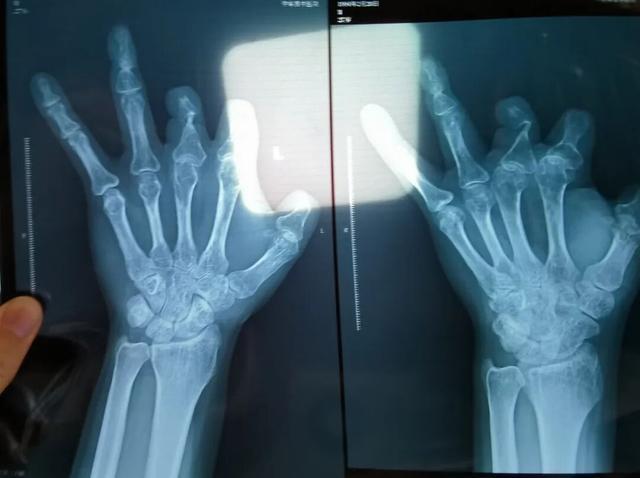

患者王海森左手拇指关节以上部位被电锯切断,收费单显示术中使用了微血管吻合装置,但X光片中未显示该器械。新京报记者 程亚龙 摄

单价1.68万元,声称在术中植入体内、用于缝合血管的两个环形吻合装置,竟然在王海森的X光片上消失了。

装置上带有不锈钢针,不可能被人体吸收,唯一的可能就是“手术时其实没有使用”。尽管之前也有其他人向王海森透露过这一点,但直到看到片子前,他一直都不相信。

该产品的代理商曾向新京报记者证实,微血管吻合装置为植入型医疗器材,患者拍摄X光片时会有显示。新京报记者获取了一位曾在郑大一附院接受手术、使用了该产品的患者的X光片,其手术部位可见一绿豆大小的光圈。

2021年12月,患者彭先生拍摄的左手X光片,未见收费单据中列出的微血管吻合装置。新京报记者 程亚龙 摄